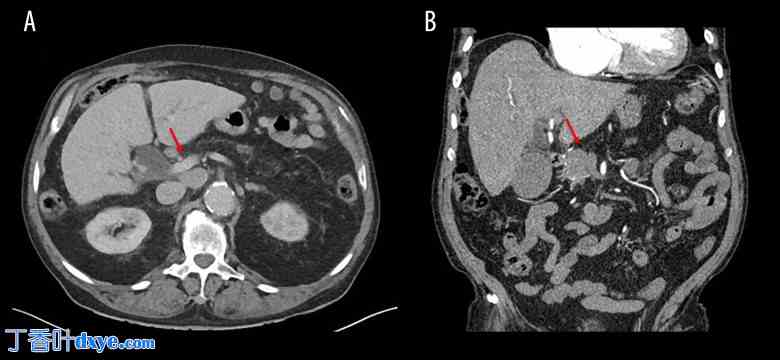

本病例报告根据基于共识的临床病例报告指南(CARE 清单) 撰写。患者为一名 86 岁男性,因突发黄疸来院就诊。病史包括慢性胰腺炎、高胆固醇血症、系统性动脉高血压和肾下腹主动脉瘤。血液检查显示患者有黄疸,总胆红素 7.5 mg/dL(正常范围 0.1 至 1.2 mg/dL),直接胆红素 6.8 mg/dL(正常值小于 0.3 mg/dL),胆汁淤积,γ-谷氨酰转肽酶 762 UI/L(正常范围 5 至 40 U/L)。其他肝脏和胰腺酶均正常。患者接受了腹部计算机断层扫描 (CT) 扫描,怀疑为胰腺肿瘤。影像学检查显示胰体尾完全萎缩,伴有3厘米胰头肿块压迫胆管,从而导致肝内外胆管扩张(图1)。肿块与肠系膜上静脉(SMV)接触,其周长约1/3(右侧),并发现多发性淋巴结肿大(主动脉间、腔静脉、胰周和肝门左侧)。肿瘤标志物(CEA、CA19.9)均在正常范围内。

图1.

增强CT扫描,横断面(A)和冠状面(B)显示胰体尾缺失,无胰腺炎。箭头指示胰头处一个3厘米肿块压迫胆管。